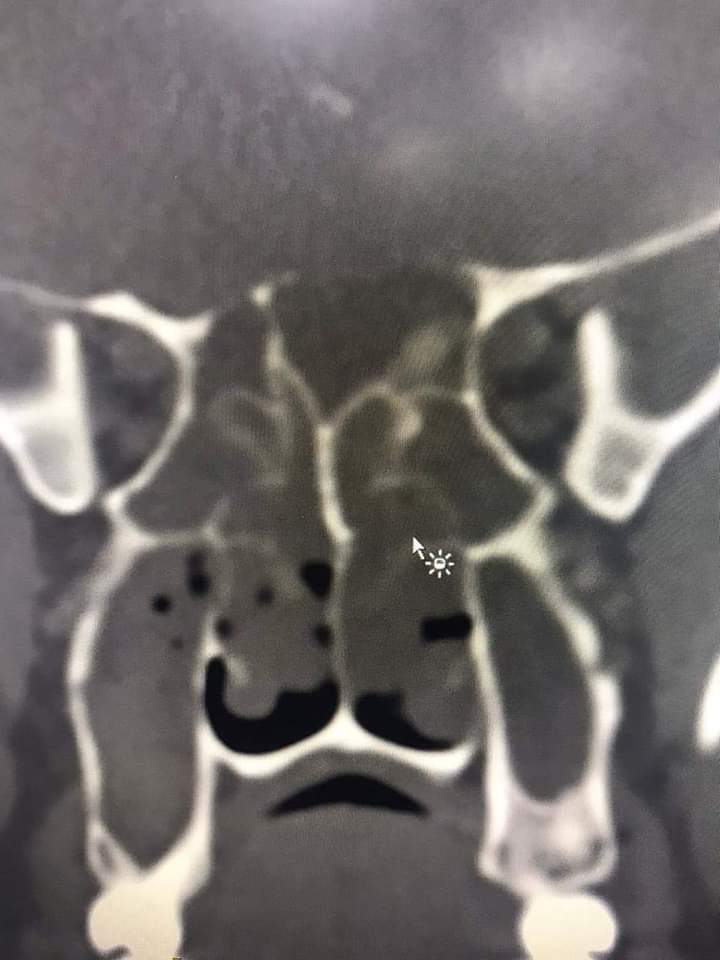

قام فريق طبي من دائرة الأذنية في الخدمات الطبية الملكية برئاسة العقيد الطبيب نبيل الشواقفة مستشار جراحة الأنف وقاع الجمجمة بإجراء عملية تنظير معقدة ونادرة لشاب يبلغ من العمر ٢٠ عاما، يعاني من التهاب فطري حاد ممتد إلى قاع الدماغ وحجرة العين مع وجود ثقب في قاع الجمجمة.

وبين الشواقفة ان المريض عندما راجع عيادة الأنف والأذن والحنجرة في مدينة الحسين الطبية كان يشكو من صداع شديد وانسداد في الأنف وصعوبة في التنفس، وبعد إجراء الفحص السريري والشعاعي تبين وجود إلتهاب حاد ممتد إلى قاع الجمجمة وحجرة العين وثقب في قاع الجمجمة، تقرر على أثرها إجراء العملية التي تعتبر من العمليات النادرة والمعقدة التي تحتاج فريق طبي متخصص .